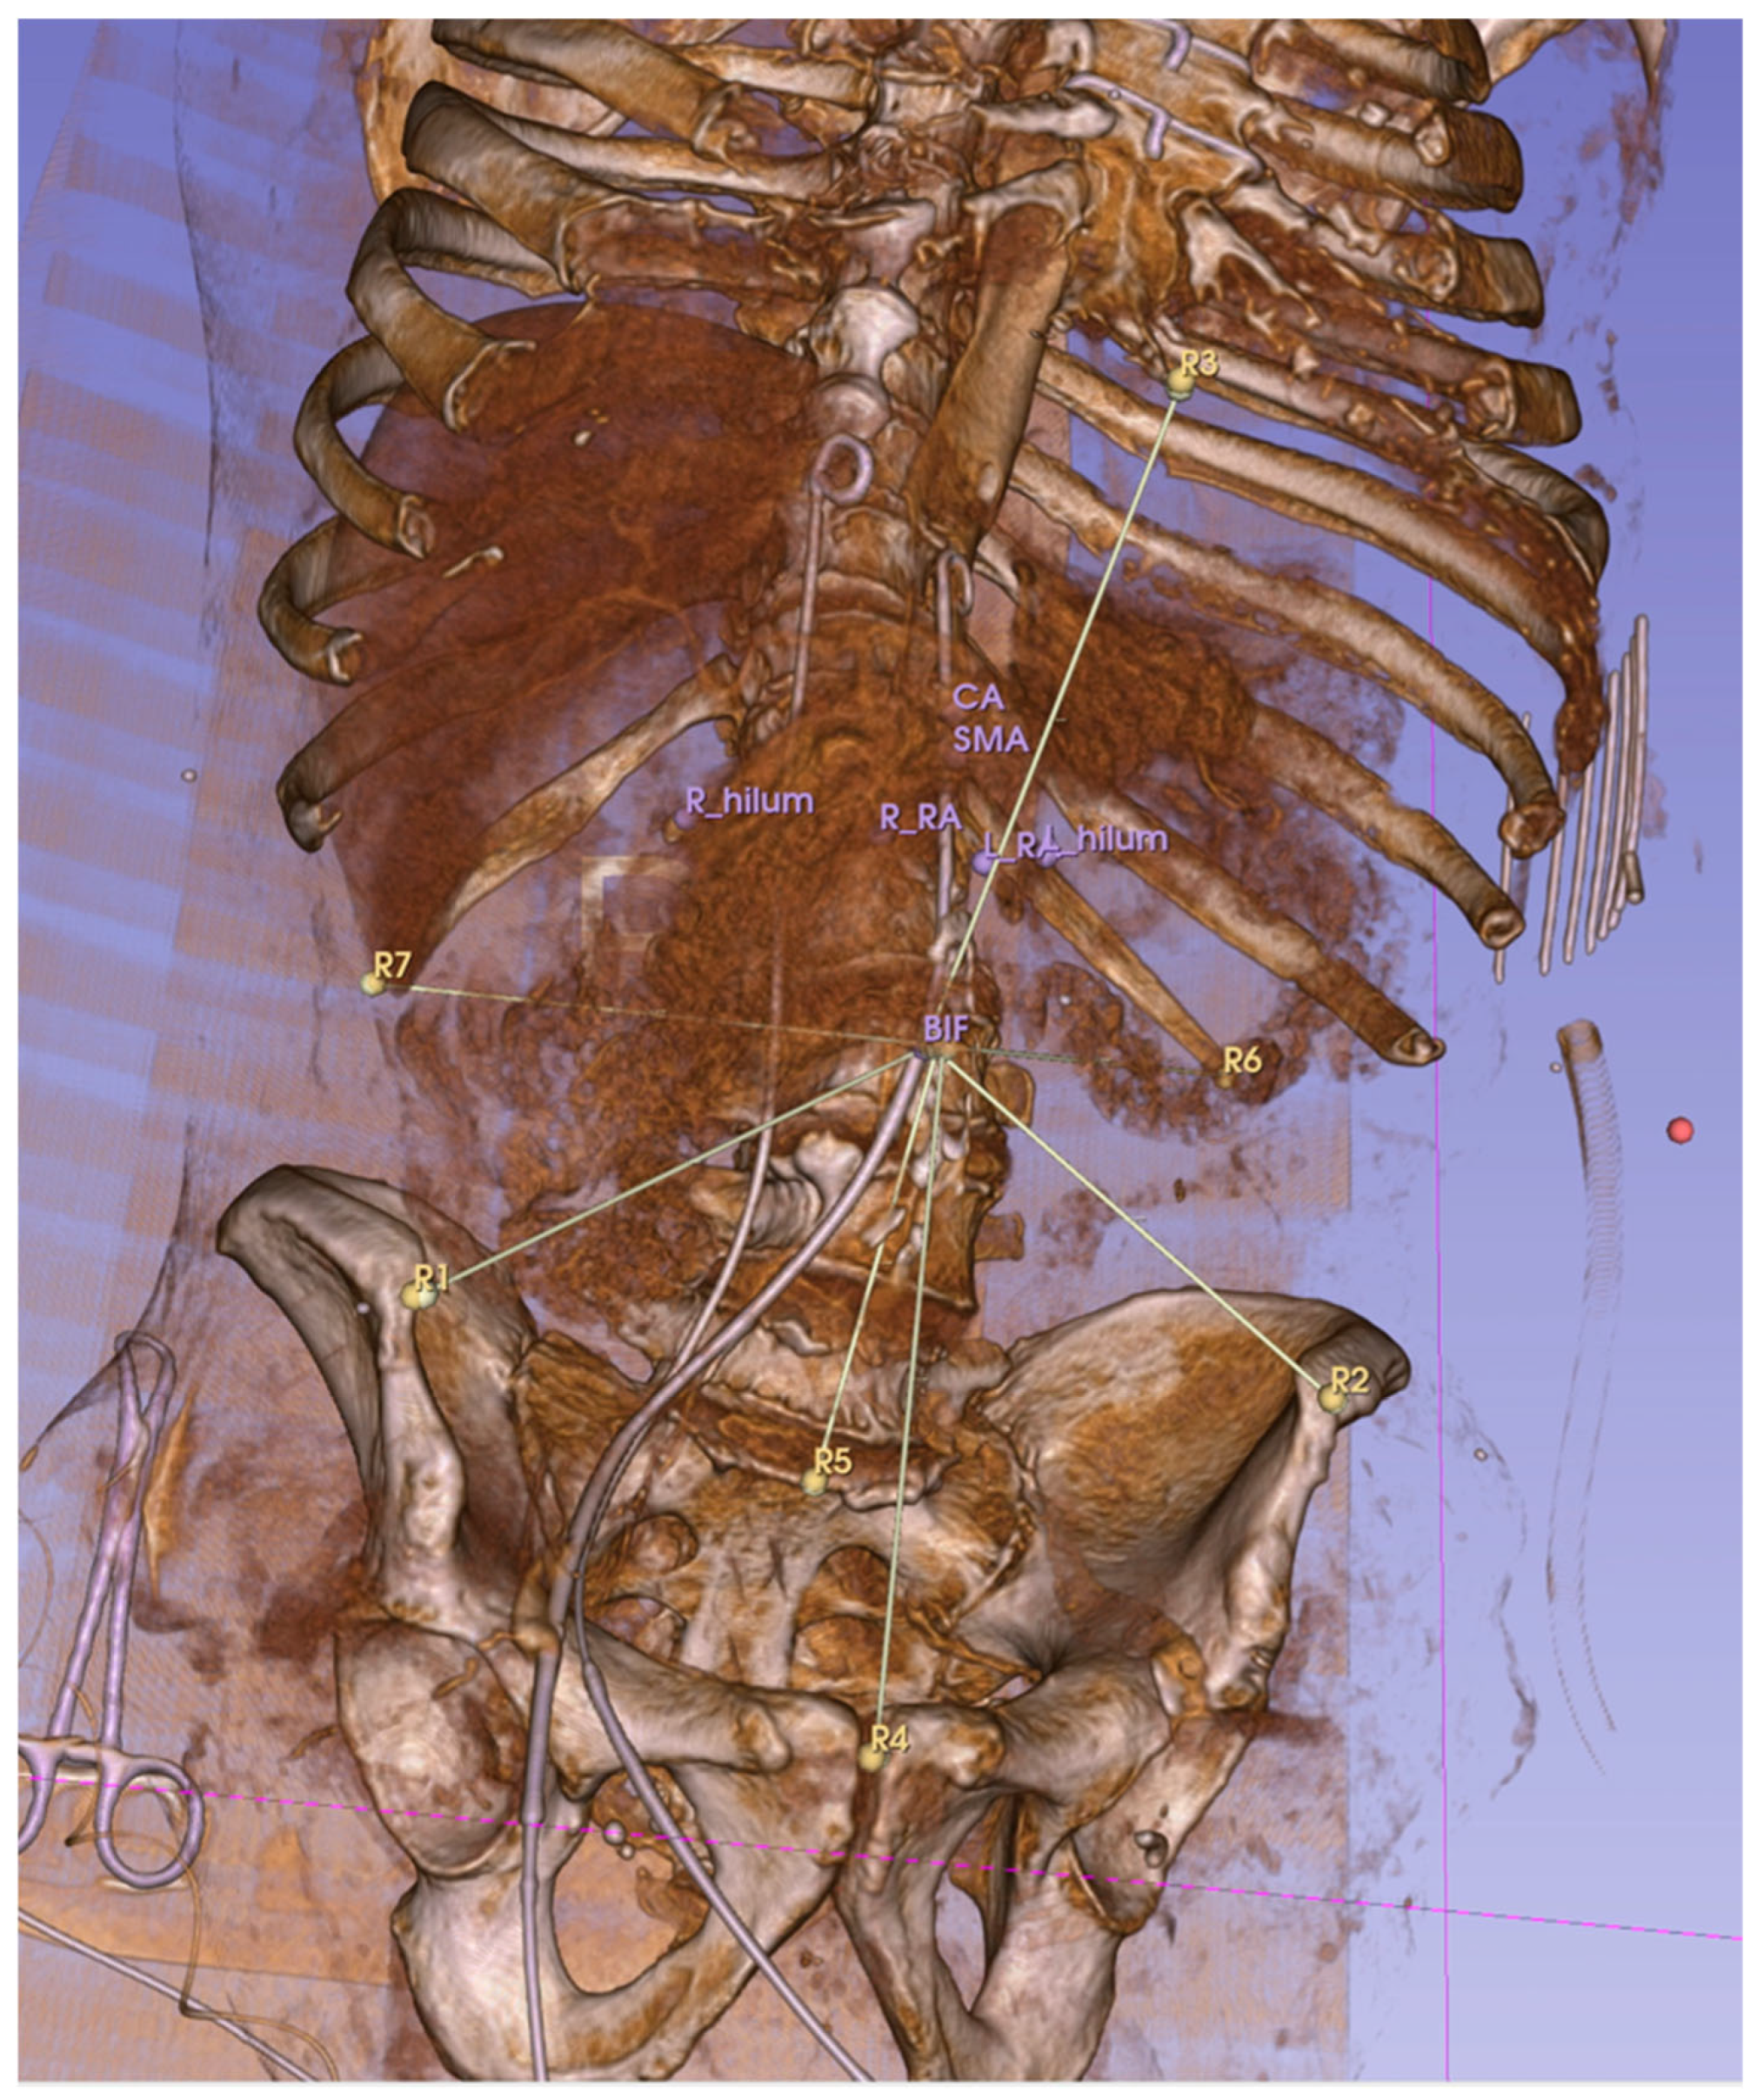

| Anatomical References | Anatomical Target Landmarks | ||

|---|---|---|---|

| R1 | Right Anterior Superior Iliac Spine | P1 | Aortic Bifurcation |

| R2 | Left Anterior Superior Iliac Spine | P2 | Left Renal Artery |

| R3 | Symphysis (upper edge) | P3 | Right Renal Artery |

| R4 | First Sacral Vertebra | P4 | Hilum of the Left Kidney |

| R5 | Tip of the Left XII. Rib | P5 | Hilum of the Right Kidney |

| R6 | Tip of the Right XII. Rib | P6 | Superior Mesenteric Artery |

| R7 * | Distal Tip of the Sternum (excluded) | P7 | Celiac Artery |